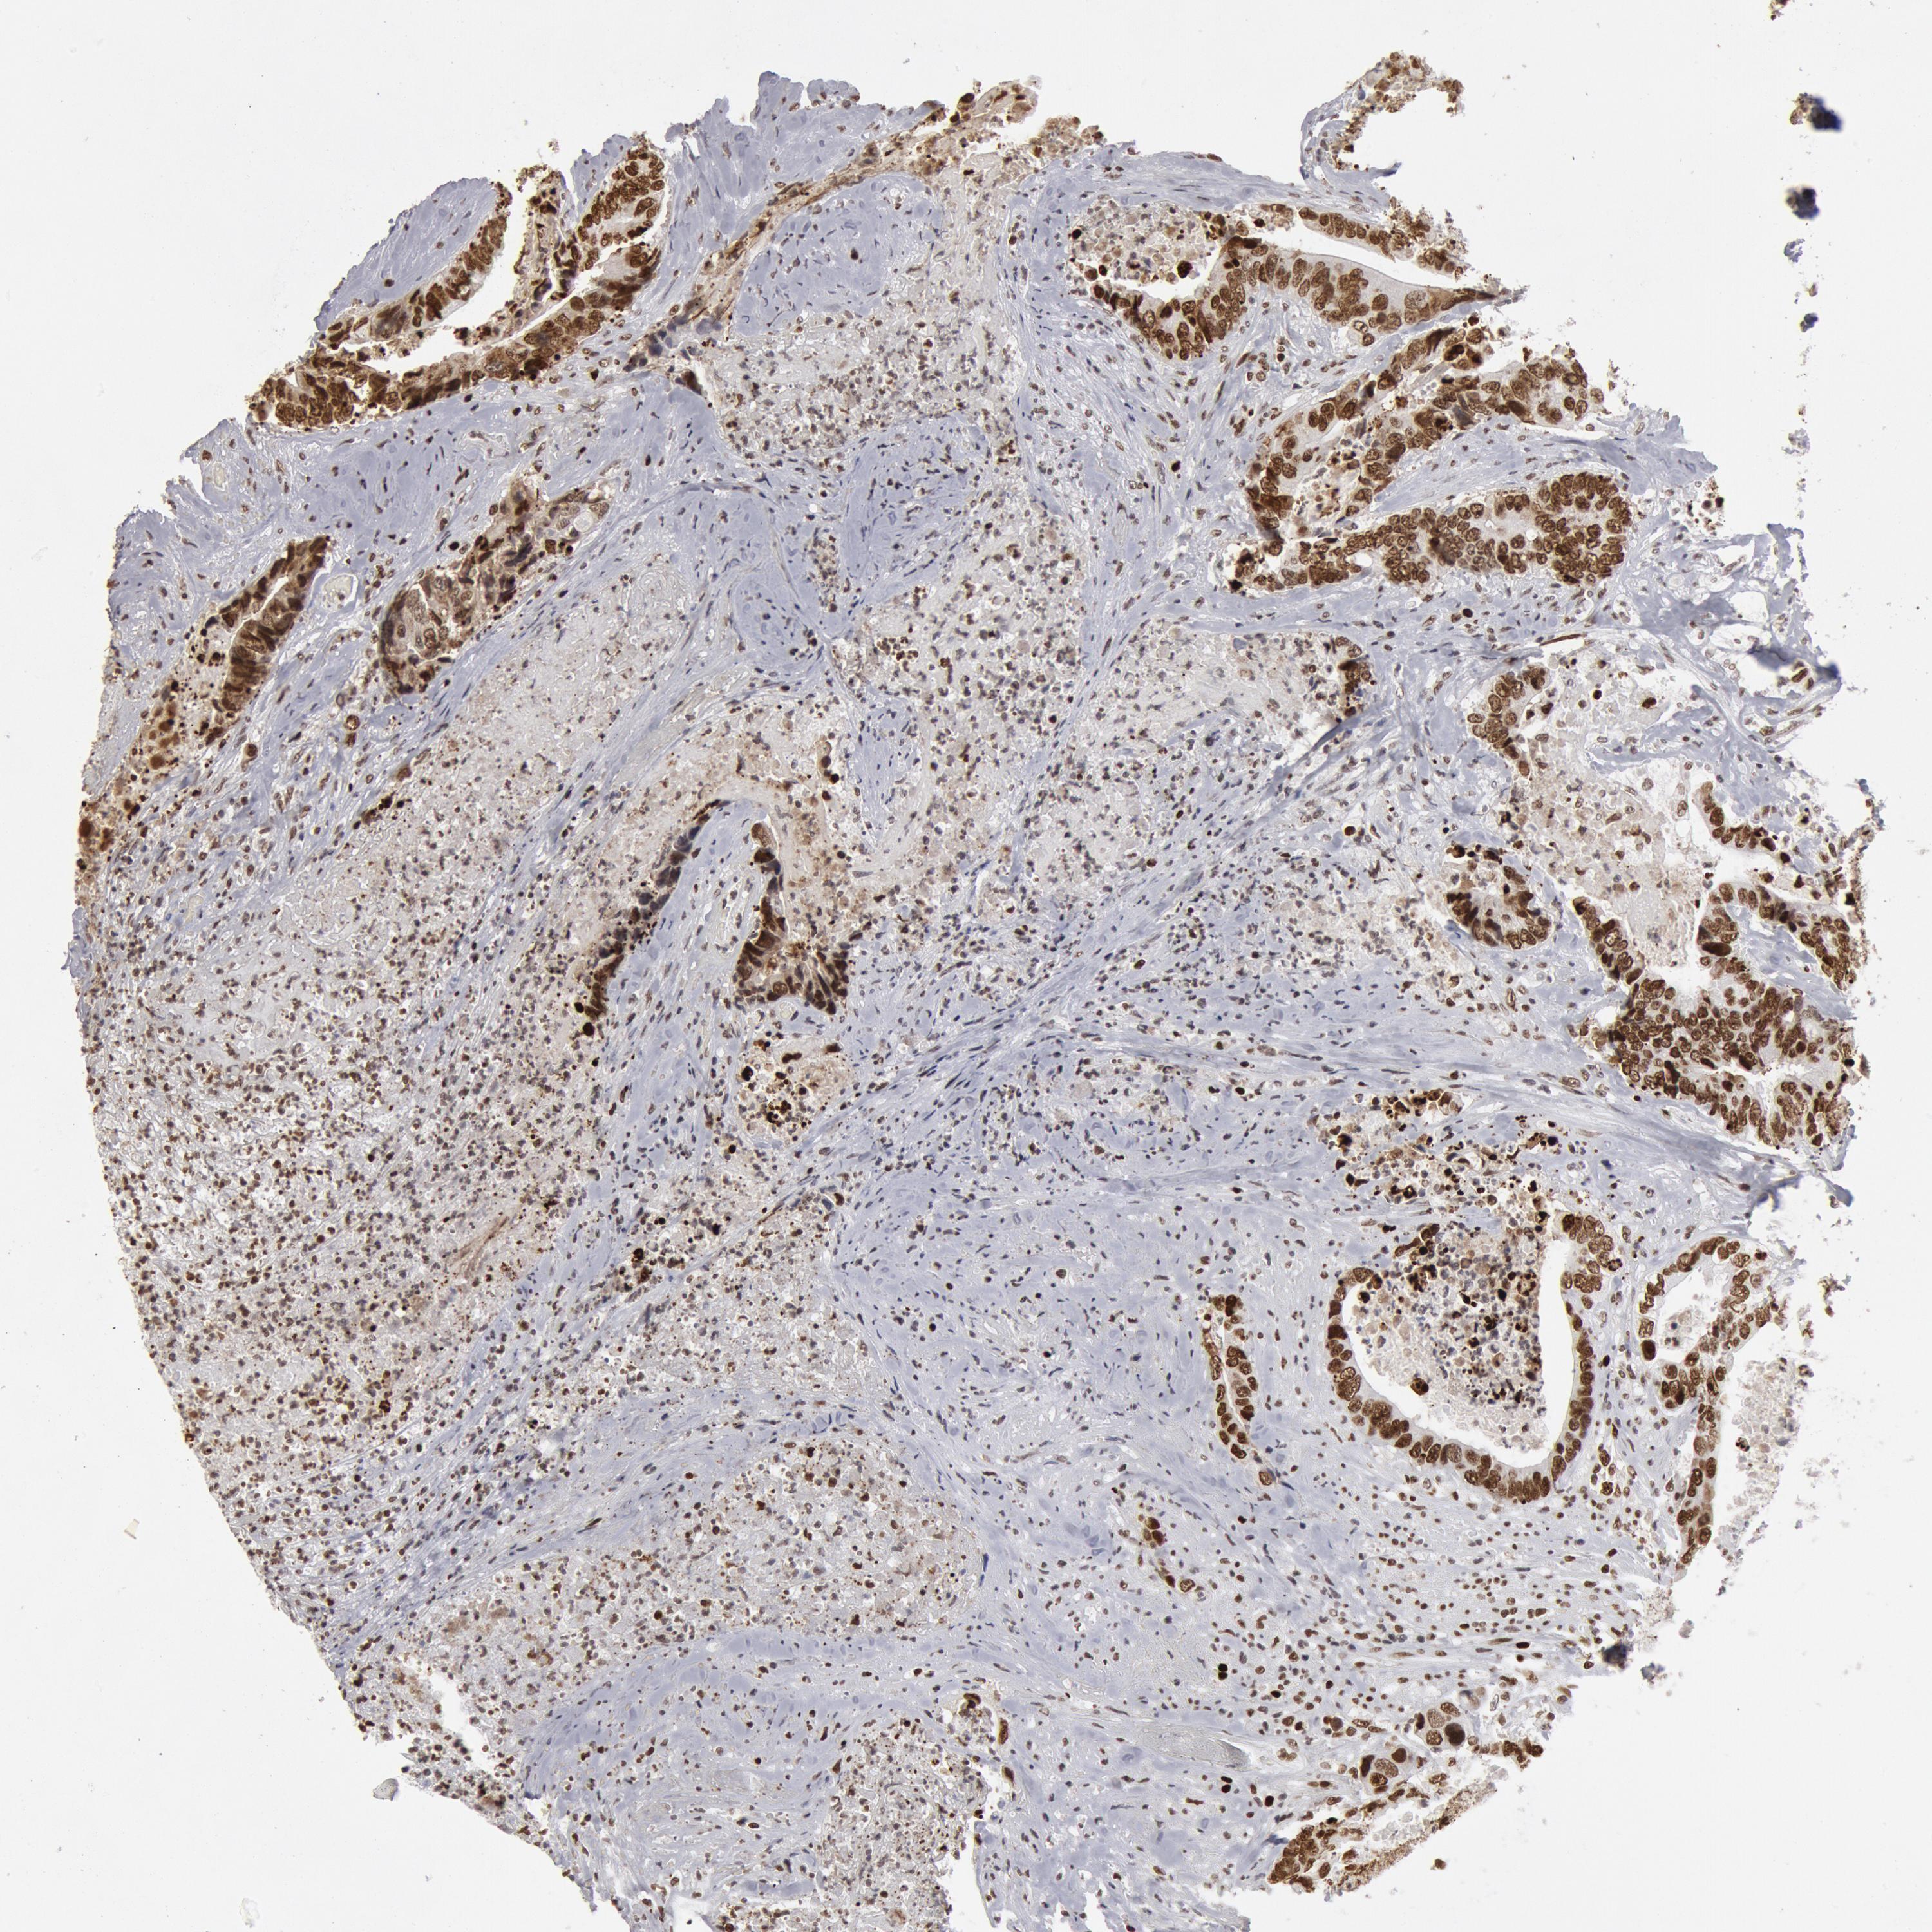

CANCER COLORECTAL CANCER Show tissue menu

ANTIBODIES

AND

VALIDATION